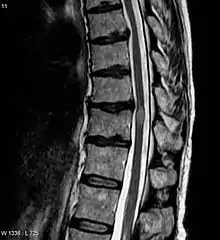

An MRI showing a transverse myelitis lesion, which is lighter, oval shape at center-right. The patient recovered 3 months later. | |